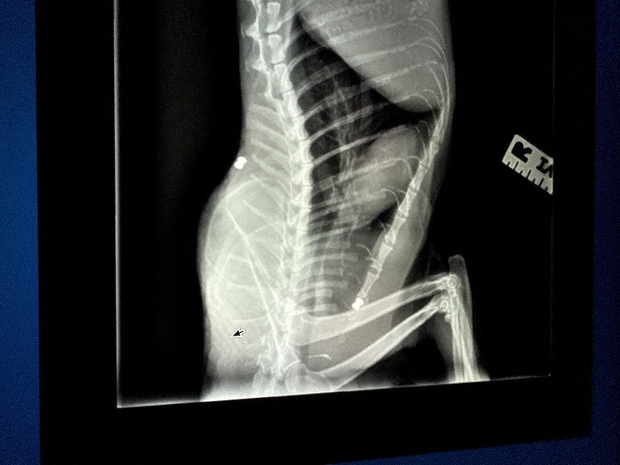

They [shared the story of Albert the cat](https://www.cbsnews.com/losangeles/news/cats-shot-with-bb-guns-rescued-by-south-los-angeles-volunteers/), who was shot in the spine with a BB gun and had a bullet lodged in his spine. At that point, People for the Ethical Treatment of Animals began working with the adoption group to care for Albert, who cannot have the bullet removed for risk of paralysis. They believe that he will likely have to be on pain medication for the rest of his life and that he will always have a limp after the shooting.

An X-ray of the bullet lodged in Albert the cat's back after he was shot with a BB gun in South Los Angeles in early March. PETA